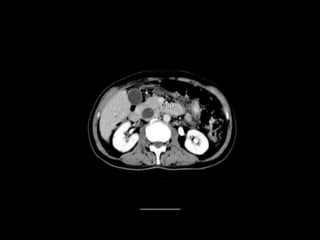

CT ABDOMEN

ANATOMY

Cross section anatomy of abdominal ct scan